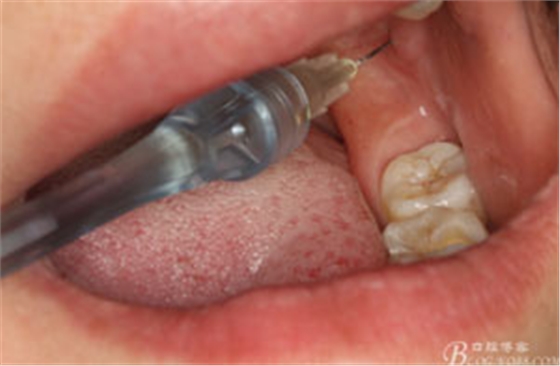

圖4.行下頜無痛阻滯麻醉

圖5.加局部浸潤麻醉